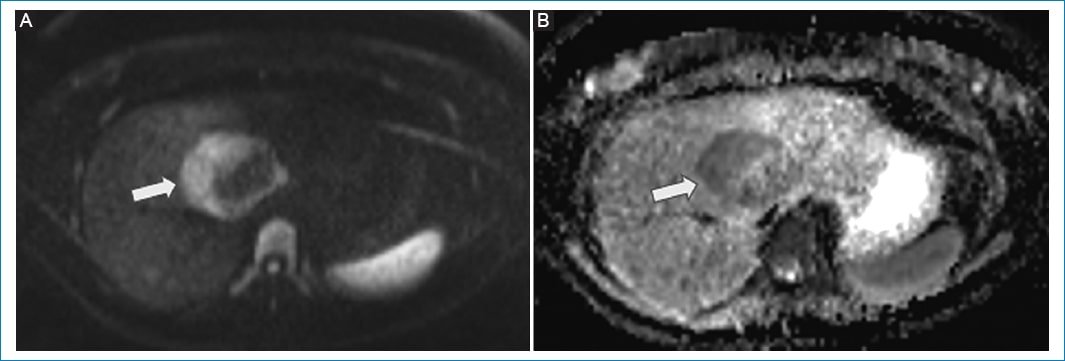

Presentamos el caso de una mujer de 34 años, sin antecedentes médicos relevantes, que fue remitida a nuestro centro por el hallazgo incidental de un tumor hepático en una ecografía debido a dolor abdominal. Se realizó una resonancia magnética (RM) hepática con contraste endovenoso en nuestro centro, que mostró una masa heterogénea en el segmento VIII-IV de 64 x 54 mm, ligeramente hipointensa en T1, ligeramente hiperintensa en T2, con restricción en difusión y realce heterogéneo con el contraste endovenoso en la fase arterial y lavado en la fase tardía (Fig. 1–Fig. 3). No se observó infiltración de estructuras vasculares. Se interpretó como una lesión maligna, pudiendo corresponder a un carcinoma hepatocelular (HCC) o a un adenoma maligno.

Figura 2. RM hepática. Axial de difusión b800 (A) y mapa de coeficiente de difusión aparente (B) muestran difusión restringida en la periferia de la lesión hepática (flechas).